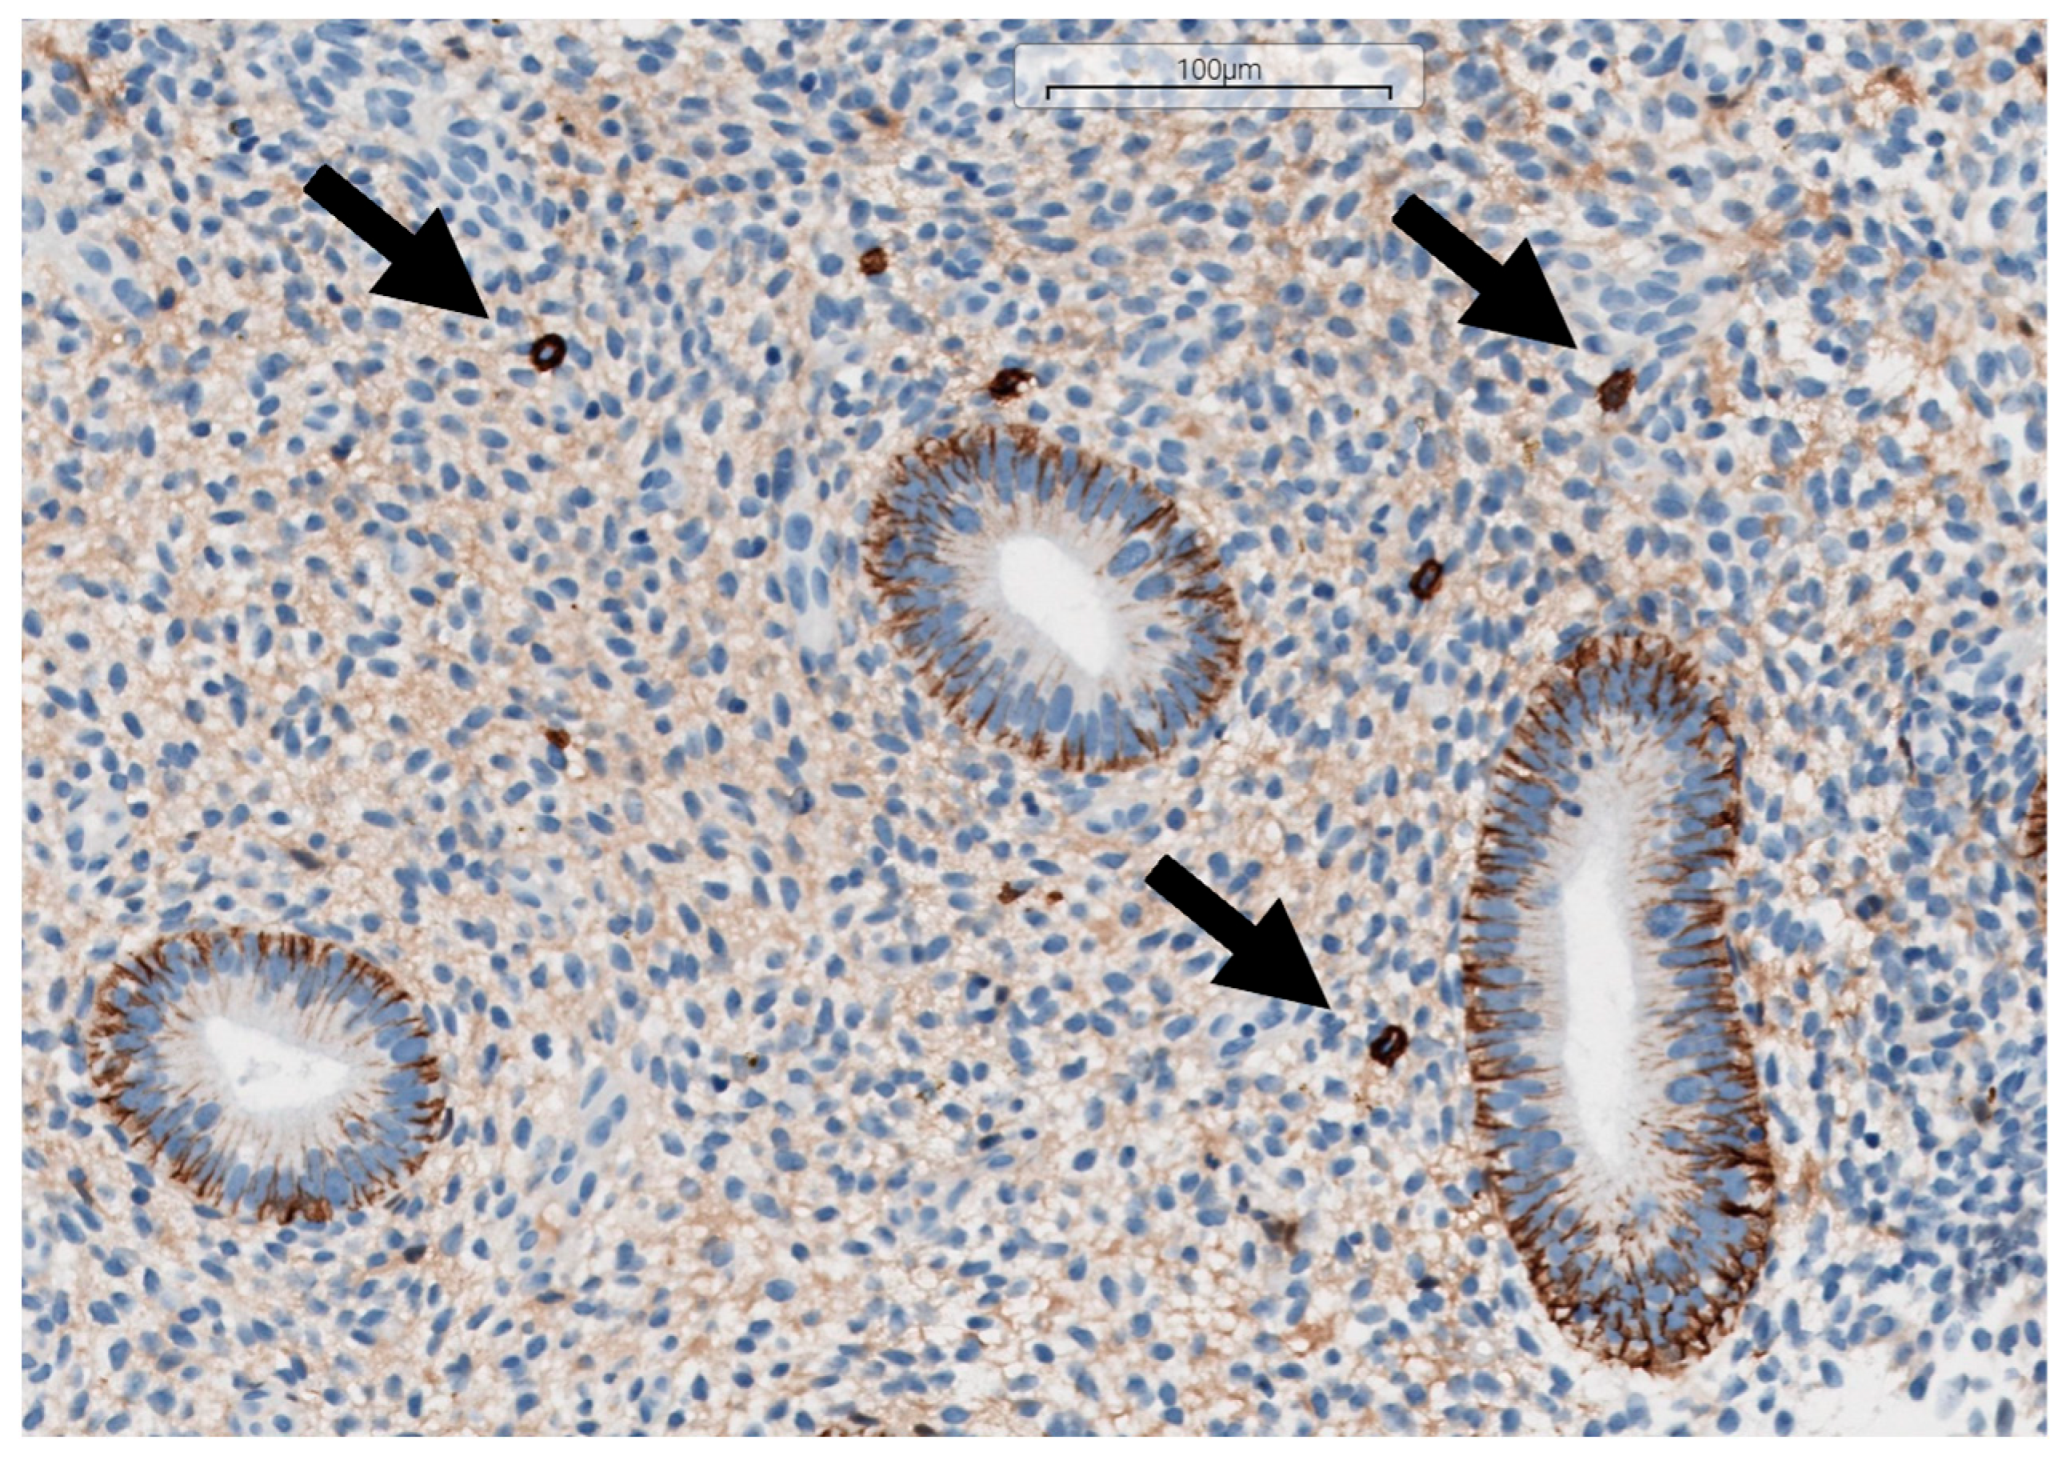

2.5. Histopathological Diagnostics